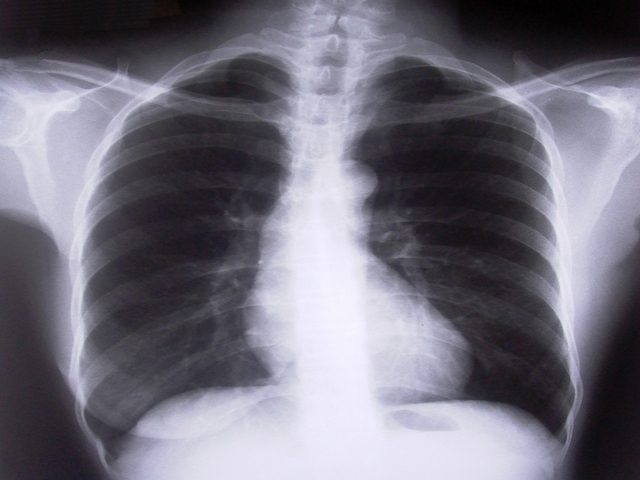

No Brasil, o câncer de pulmão é a principal causa de morte entre homens e a segunda entre as mulheres. O oncologista também comentou que entre os sintomas da doença estão tosse, falta de ar, dor ao respirar, chiado no pulmão e presença de sangue ao tossir.